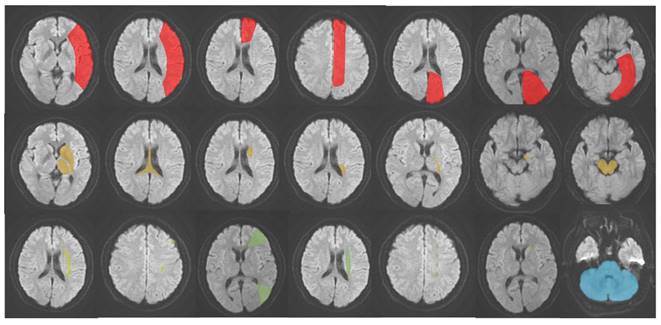

AIS was classified into five subtypes based on its occurrence in different locations: (1) LTI of anterior cerebral artery (ACA), middle cerebral artery (MCA), and posterior cerebral artery (PCA); (2) DPI of ACA, MCA and PCA; (3) SPI of MCA; (4) WI; (5) IFI [14-17]. The schematic diagram of the classification is presented in Figure 2. Hyperattenuating on DWI and hypoattenuating on ADC were defined as an ischemic core.

Figure 2

The schematic diagram of AIS classification. Red: large vessel trunk infarction; yellow: deep perforator vessel infarction; light yellow (lime): superficial perforator vessel infarction; green: watershed infarction; blue: infratentorial infarction.